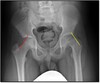

5